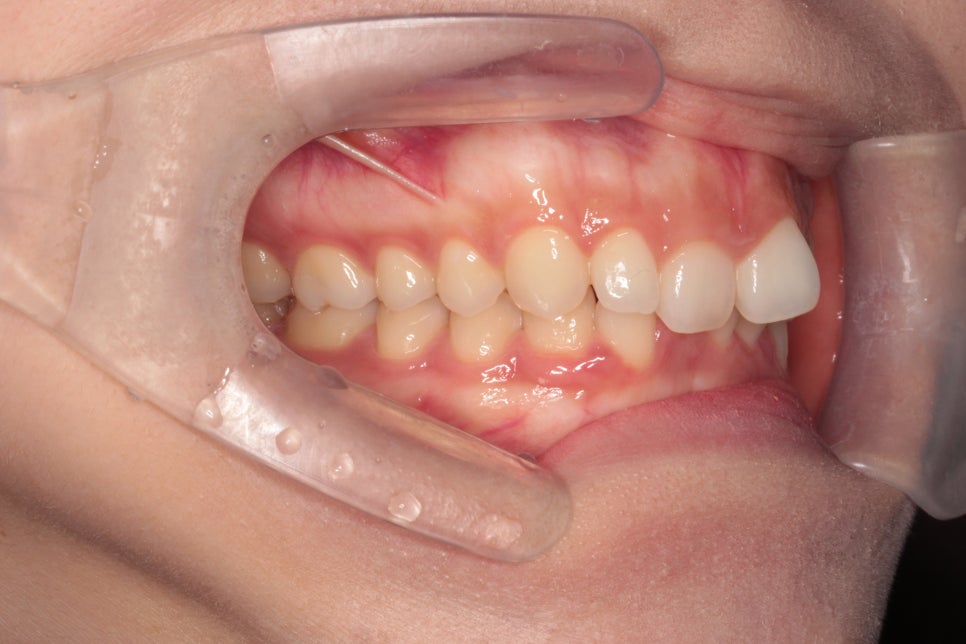

이 사진은 첫날 인비절라인을 착용하였을때의 사진입니다.